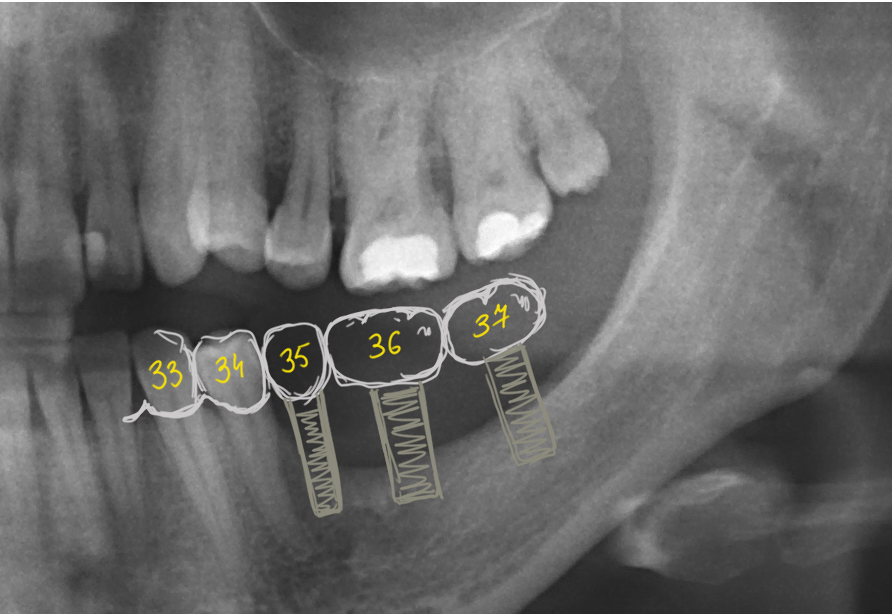

Контрольный снимок.

Обычно для послеоперационного контроля достаточно даже прицельного снимка. Но мы делаем ортопантомографию:

А в некоторых случаях — конусно-лучевую компьютерную томографию.

По снимку мы проверяем отношение имплантата с окружающими тканями (в первую очередь) с верхнечелюстной полостью, а также посадку формирователя десны. Между ними не должно быть щели — это особенность систем с плоской платформой.